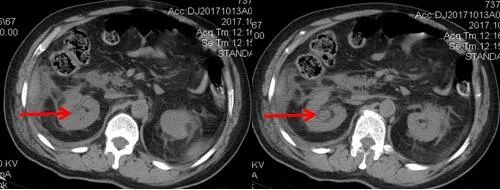

術(shù)后CT,箭頭所指為腎結(jié)石被徹底清除